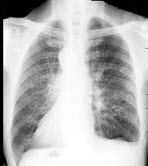

136、单项选择题

女,11岁,低热,夜间盗汗,咳嗽1月余,结合图像,最可能的诊断是()

A.支气管肺炎

B.肺结核

C.肺癌

D.过敏性肺炎

E.大叶性肺炎

点击查看答案